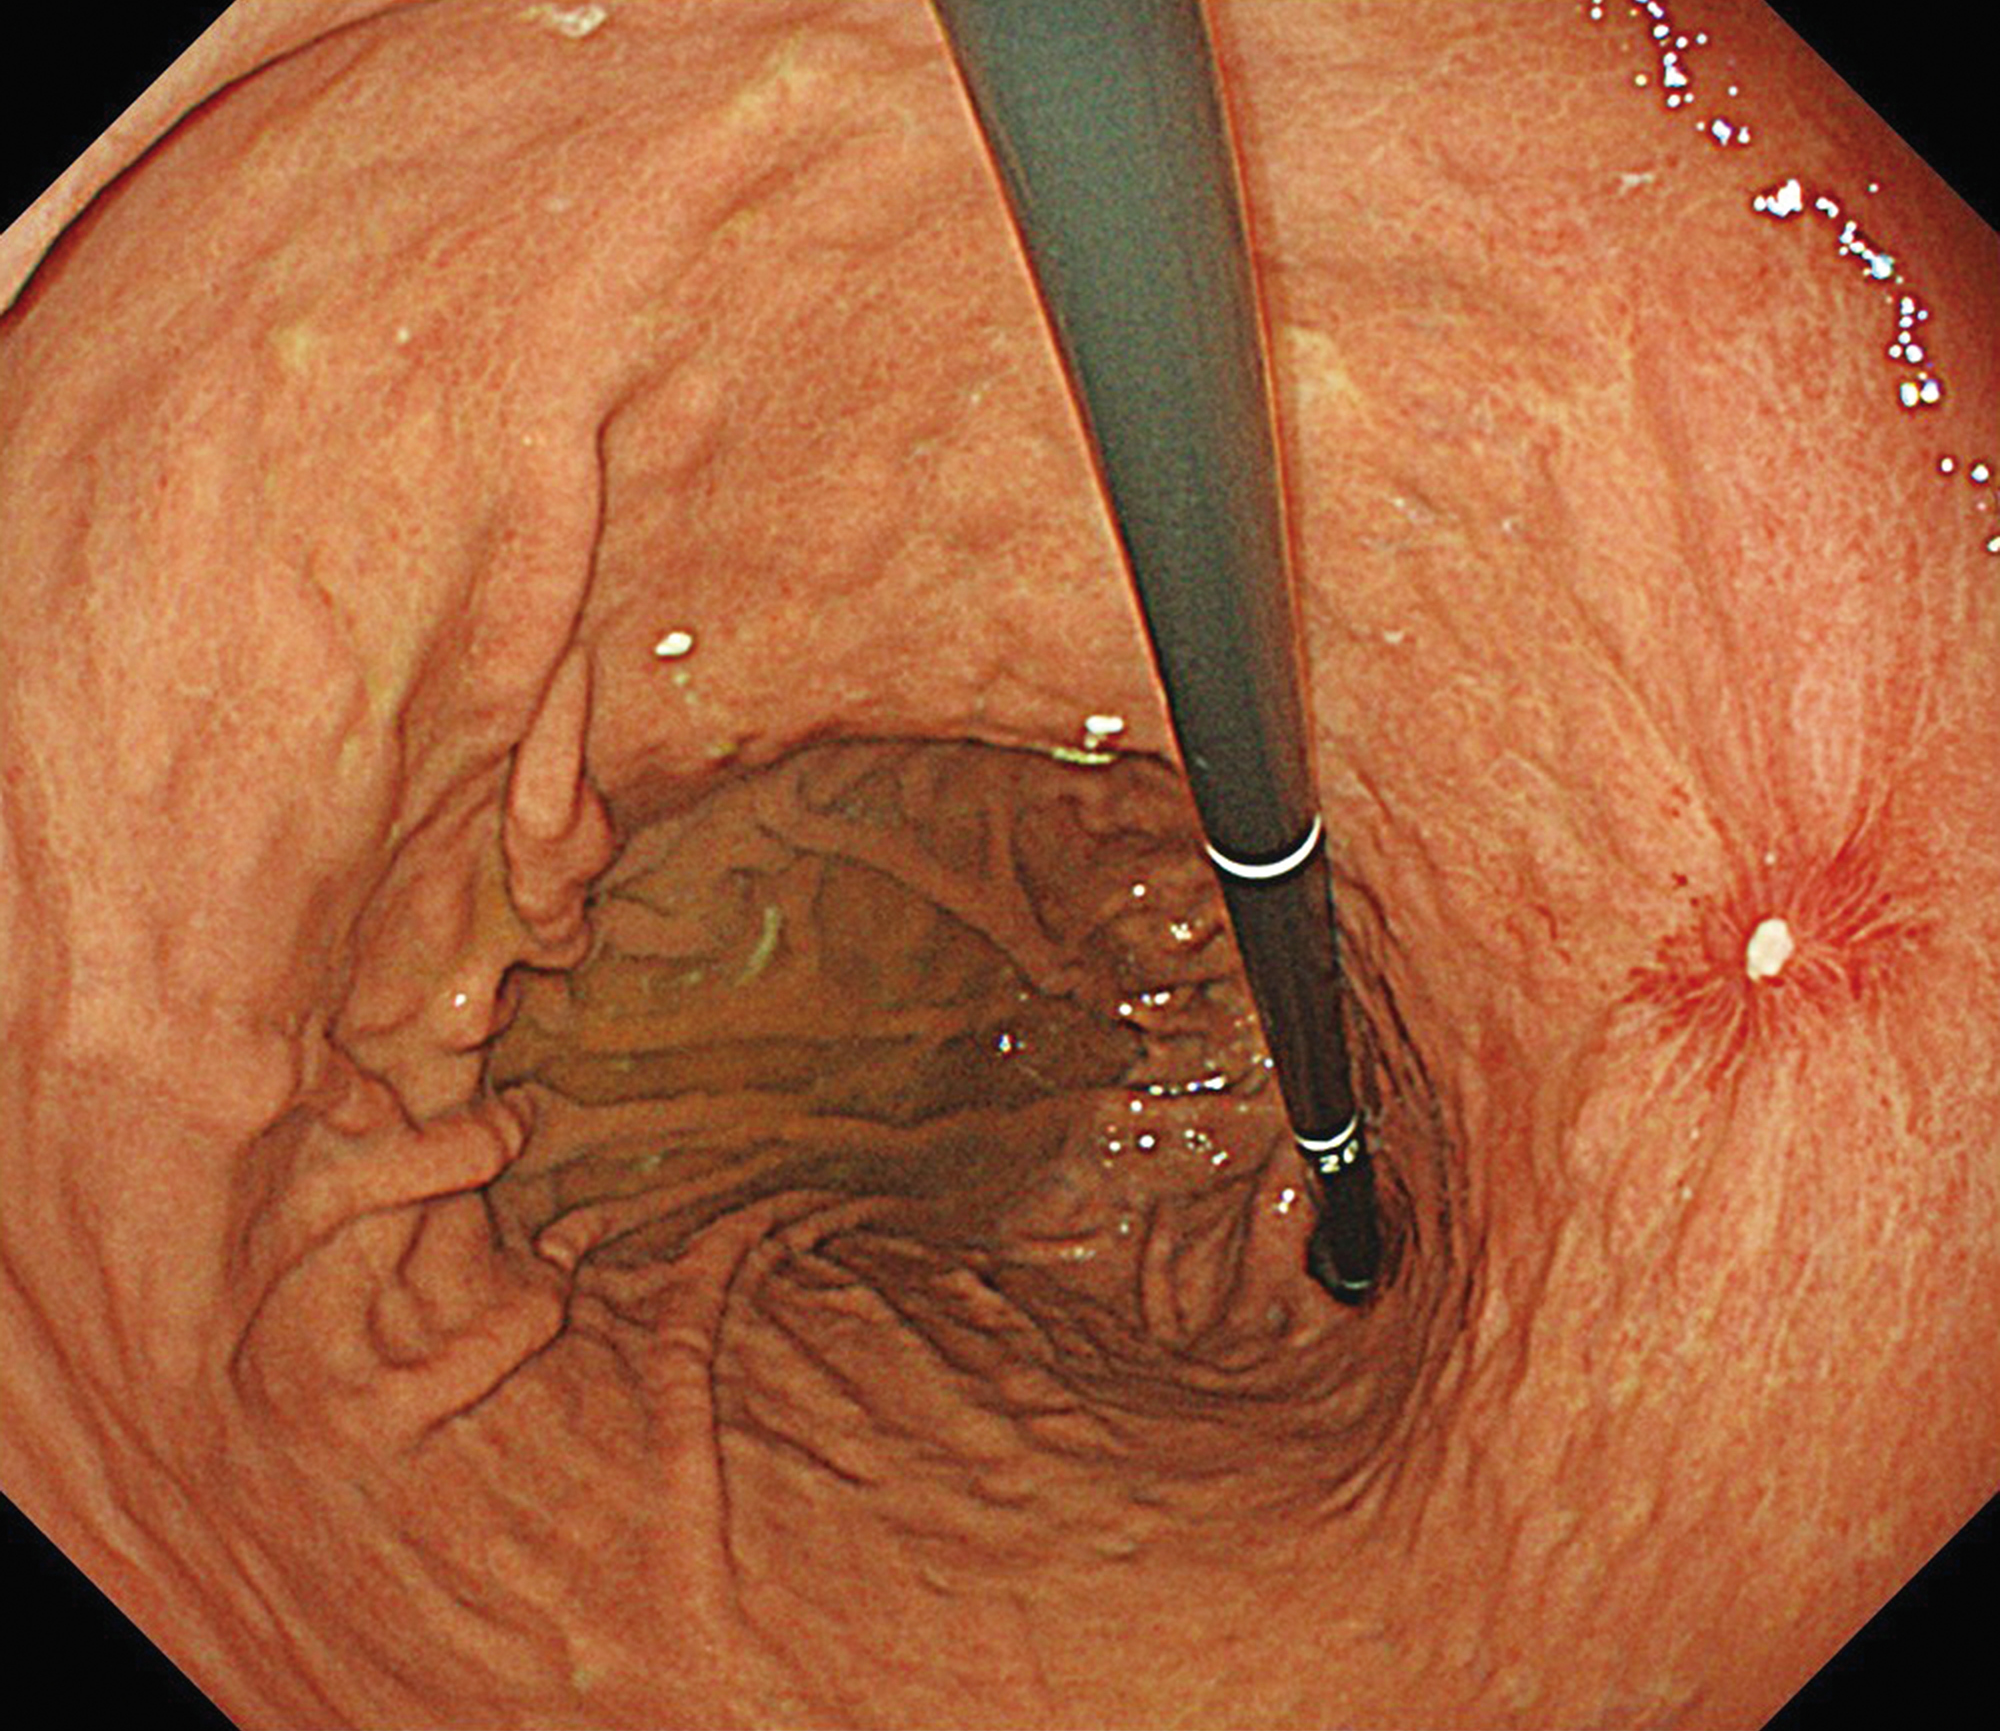

EVIS X1×GIF-1200N 症例画像

下部食道 NBI